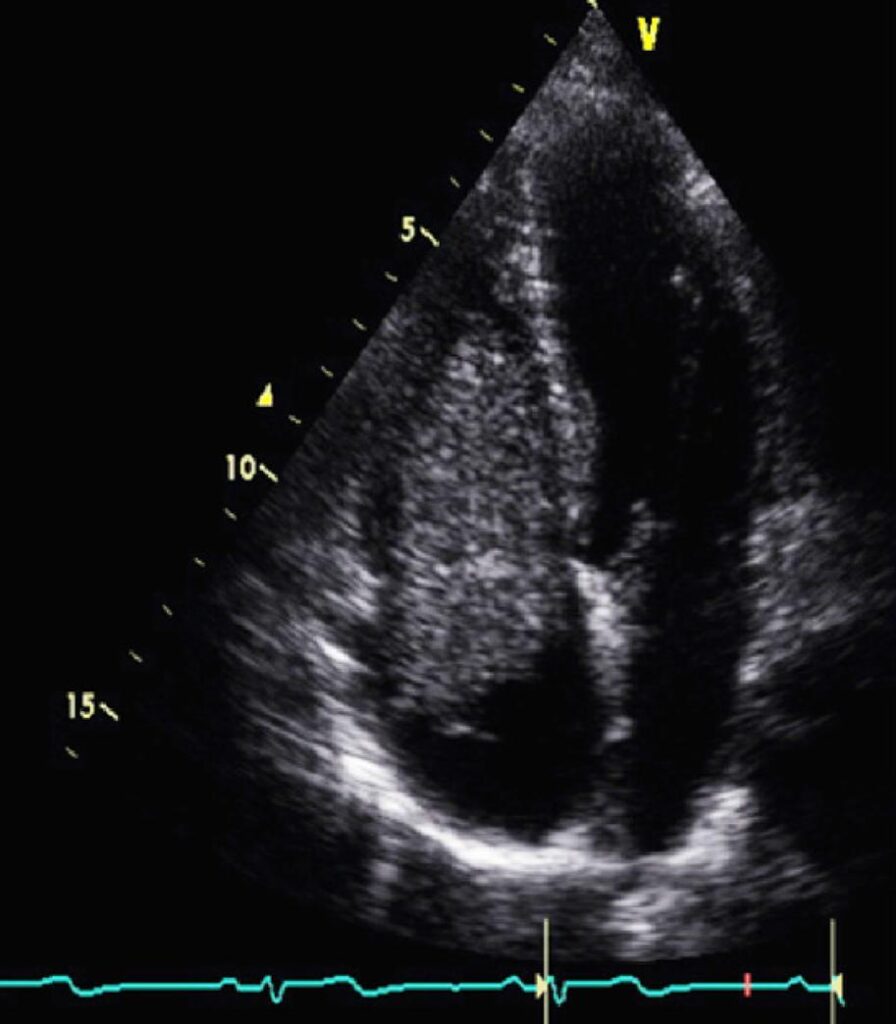

Terceira Recorrência de Mixoma Cardíaco em Paciente com Complexo de Carney

Os tumores cardíacos primários são uma entidade incomum e apresentam uma incidência de 0,3% a 0,7%. Os tumores benignos constituem a maioria das neoplasias cardíacas primárias, e o Mixoma Cardíaco (MC) é o tipo mais prevalente. , Os pacientes com MC podem apresentar sintomas devido a fenômenos embólicos ou obstrução intracardíaca do fluxo sanguíneo, e o tratamento é a resseção cirúrgica. , A recorrência tumoral pós-operatória pode ser observada em até 3%, porém, quando os mixomas ocorrem como parte de uma síndrome genética subjacente, a taxa de recorrência pode chegar a 22%. A principal síndrome associada com essa recorrência é o Complexo de Carney (CNC). Descrito pela primeira vez em 1985 por J. Aidan Carney, o CNC é definido como uma síndrome genética autossômica dominante extremamente rara, e suas principais características clínicas incluem pigmentação cutânea, mixomas predominantemente do coração e neoplasias endócrinas.

Palavras-chave: Complexo de Carney; Ecocardiografia; Mixoma